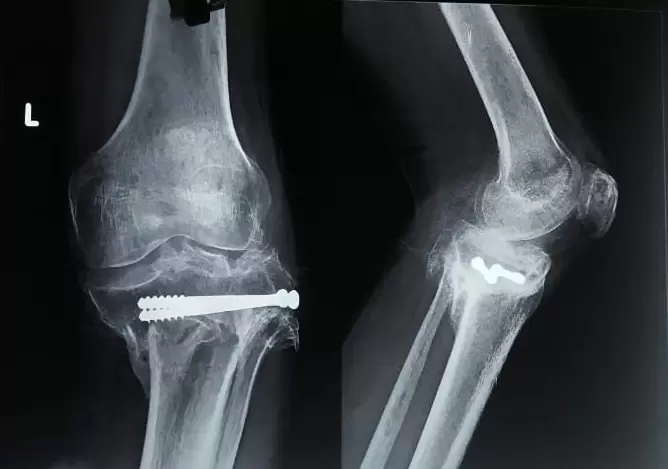

A 47-year-old patient had sustained a fracture of his leg bone (tibia) 10 years ago which was treated elsewhere with surgery.

Although his fracture had healed, it had healed in a wrong position causing him pain and difficulty in walking.

However, the challenges were, deformed leg bone (tibia) owing to the previous fracture, young age of 47 years, ligament imbalance owing to the long duration of deformity, and financial constraints of the patient.

We performed a Total knee replacement (TKR) on him using the Stryker Triathlon system, which is a very advanced and versatile knee replacement device that provides a very high degree of knee bending.